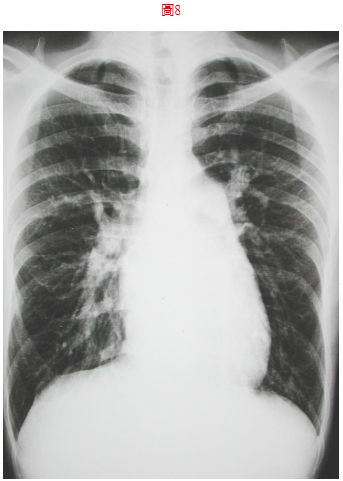

8. 病人26歲男性宜蘭頭城工人,主訴偶有胸悶歷經一個月。他自小開始就不適運動,胸口時有鐘擺劇動,最近常有運動相關的胸悶,伴有心悸眩暈,有時強度運動會有發紺。既往病史未有特別,理學檢查; 身高155cm, 體重45.5 kg, 血壓108/70 mmHg, 心跳80/min, 頸靜脈正常PMI 左5th ICS的LMCL, RV heave, 在左上胸椽有Gr III/VI systolic ejection murmur with fixed splitting S2, 未有心雜音傳移, P2加重。其他理學未有不正常,胸部X光如圖8及心電圖 如圖示,本病人最正確的心臟診斷是

(A) Pulmonary stenosis (B) Idiopathic pulmonary hypertension (C) Atrial septal defect (D) Aortic stenosis (E) Mitral stenosis